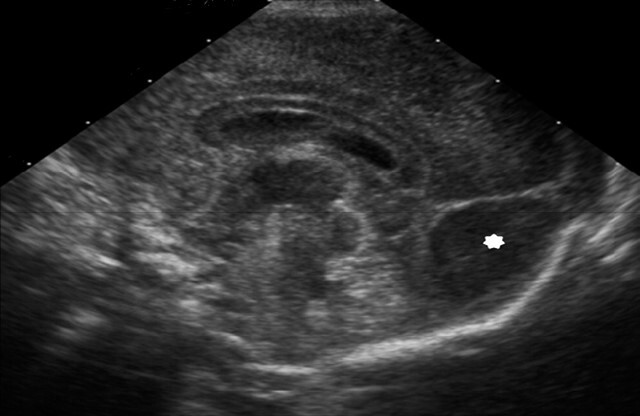

Neonatology Occipital Pseudomass Image